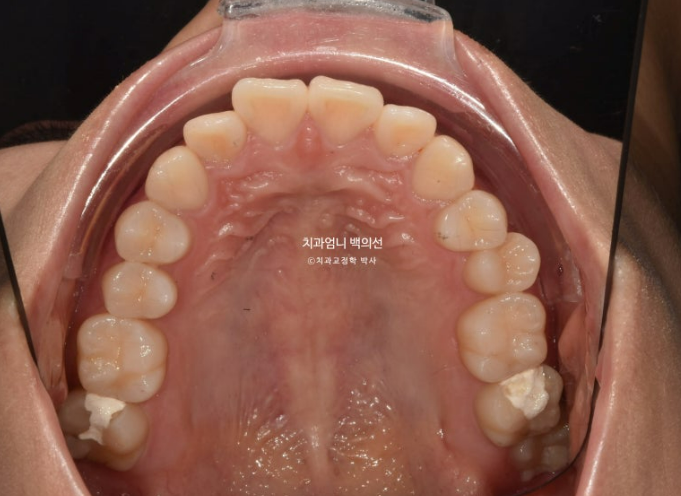

부분교정에서는 앞니 배열될 공간을 소량의 치간삭제로 얻습니다.

앞니부분교정용 장치 중 MTA 장치를 선택하셨고 치료에 들어갔습니다.

MTA 장치는 송곳니부터 송곳니까지 앞니에만 붙여서 배열을 진행했고 나머지 작은어금니와 큰어금니는 움직이지 않았습니다.

24년 9월 드디어 치료가 마무리 되었습니다.

유지장치까지 붙은 모습입니다.

총 치료기간은 9개월입니다.